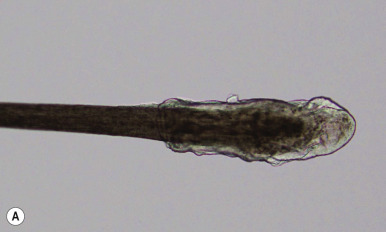

Loose anagen syndrome occurs in 10% of all children who have alopecia and is characterized by actively growing anagen hairs that are loosely anchored and can be easily and painlessly pulled from the scalp. Although considered an autosomal dominant disorder, most cases are sporadic and occur in girls. A mutation in a hair keratin ( KRT75 , formerly called K6hf ) has been found in some families, but its relevance is unclear because it does not reliably segregate with the loose anagen phenotype. Most patients are blond girls above the age of 2 years (mean, 6 years of age). Affected children generally have sparse, short, scalp hairs that seldom require cutting ( Fig. 7-11, A ). Examination shows patchy or subtle diffuse thinning with hairs of uneven length. The hair often appears to be limp, and a matted texture has been noted, particularly in occipital hair. Of the actively growing anagen hairs, more than 80% show ruffled cuticles and pigmented misshapen bulbs ( Figs. 7-11, B and C ). Gentle pulling tends to yield several hairs, allowing the diagnosis to be made by light-microscopic examination of hair; forceful extraction of hairs may lead to misshaping of normal anagen hairs and thus should be avoided. Shedding of the hair is cyclic, and the inability to extract large amounts of hair by gentle pull test does not definitively rule out the diagnosis. Although no treatment is available for this disorder, it is reassuring for patients and their families to know that other abnormalities are not associated with this disorder and individuals with this condition tend to improve with time.

The average human scalp contains 100,000 hairs. The average growth rate of terminal hair is approximately 2.5 mm/week (1 cm/month). The hair shaft represents the equivalent of the stratum corneum of skin, with the follicular keratinocytes dictating the characteristics of the shaft. The hair root is characterized by three definable cyclic stages of growth: anagen ( Fig. 7-1, A ), catagen, and telogen ( Fig. 7-1, B ; Box 7-1 ). The human hair follicle has a fairly long phase of regular growth (the anagen phase) that lasts 2 to 6 years, with an average of 3 years. The hairs then undergo a period of partial degeneration (the catagen phase), lasting up to 3 weeks, followed by a resting (telogen or club) phase. The telogen phase of the follicle lasts for about 3 months. At the end of this time, new growth is initiated. As new hairs grow, they push out the old telogen hairs that have remained in the resting follicles. In healthy individuals, 85% to 90% of the scalp is in the actively growing anagen stage, and 1% is in the brief transitional (catagen) stage; 10% to 15% is in the resting or telogen stage, with an average of 50 to 100 hairs shed and simultaneously replaced each day. Although scalp hair has a long anagen phase, eyelash and extremity hair have a lower anagen/telogen ratio and thus tend to be shorter.